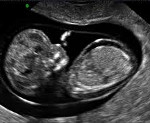

Ведущую роль в инструментальной диагностике водянки плода играет УЗИ. Ультразвуковое сканирование позволяет поставить предварительный диагноз еще в антенатальном периоде. К УЗ-признакам, которые могут указывать на водянку плода, относятся отечность плаценты, многоводие, наличие жидкости в полостях организма ребенка, гепатоспленомегалия, отек подкожной жировой клетчатки, «поза Будды». Постнатальное УЗИ выполняется для подтверждения опасных патологических состояний (гидроперикард, гидроторакс, асцит) и определения терапевтической тактики. Также могут применяться ЭКГ, компьютерная и магнитно-резонансная томография с целью дифференциальной диагностики и оценки структуры внутренних органов.